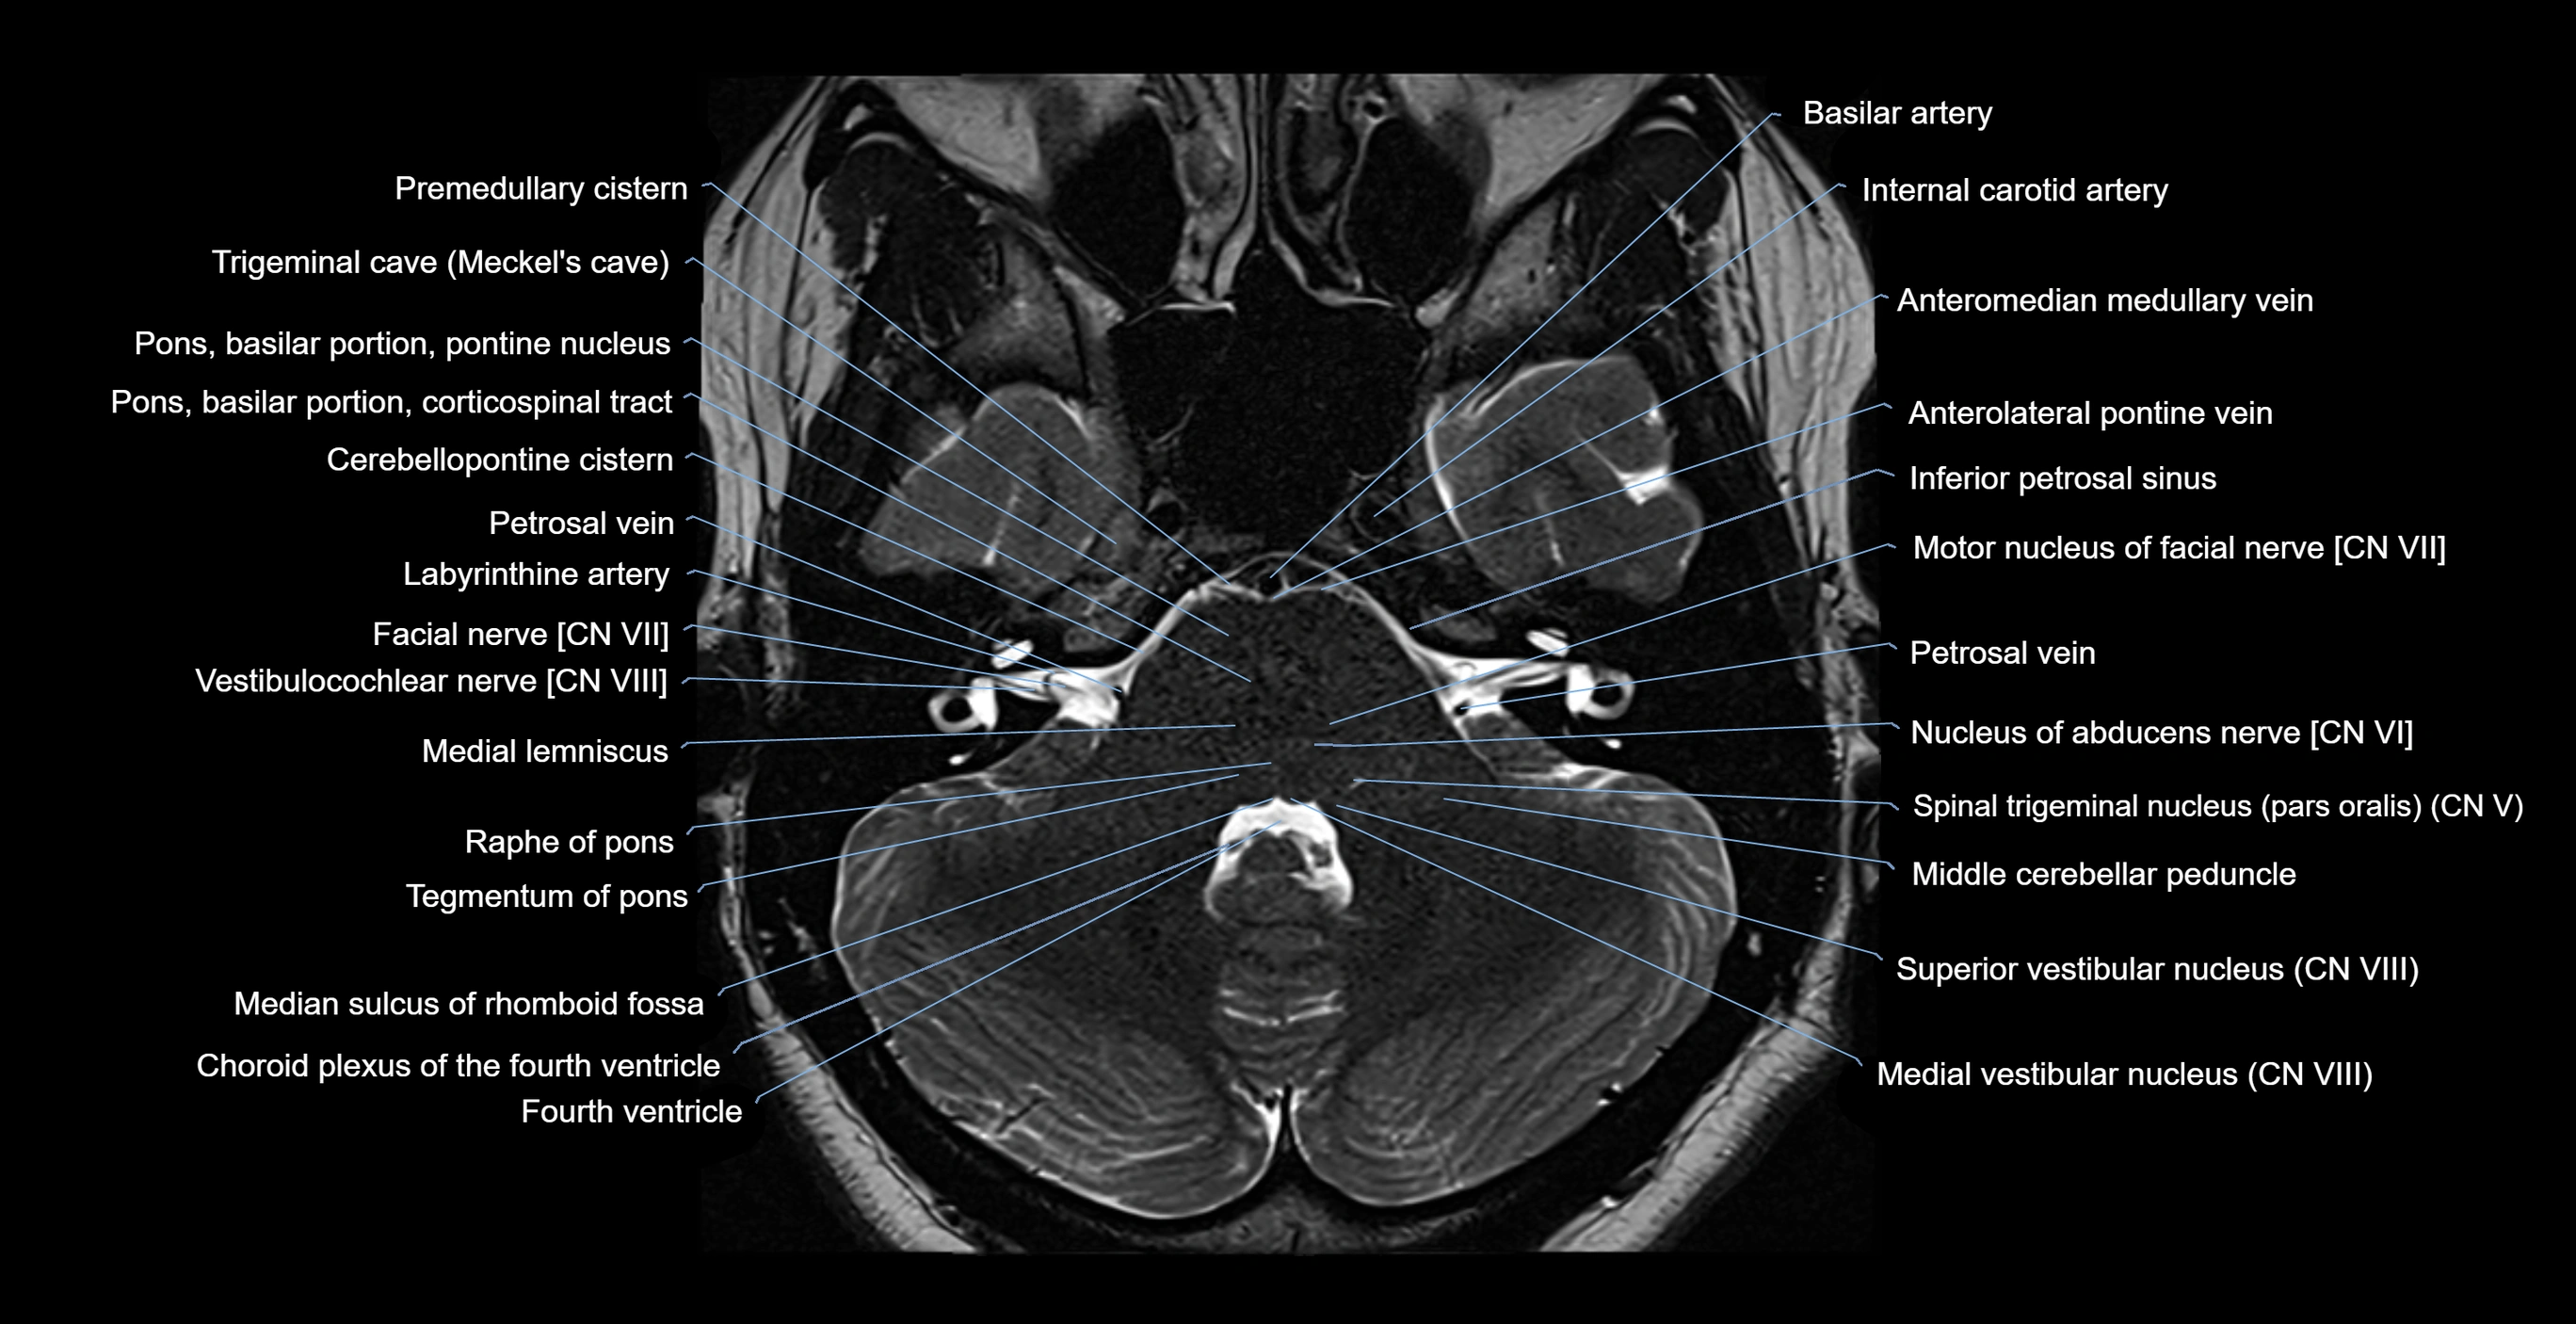

MRI images